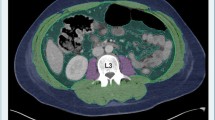

Patients (n = 3) whose CT quality was not suitable for analysis on ImageJ software due to artifact or a restricted field of view for waist circumference or skeletal muscle mass measurement were excluded. The measurement technique is detailed in a previously published article by Gomez et al. [11] and summarized in Fig. 1.

Measurement technique summarized in three steps. Step 1: after adjusting the image threshold between − 250 and + 1000, we click on the outer surface of the threshold-highlighted area with a wand tracing tool which delineates the abdominal perimeter (yellow contour in 1a). Step 2: the image returns to its original gray color after adjusting the threshold between − 250 and − 250 and we remove the yellow line by clicking on freehands selection tool. A stylus is then used to trace the outer muscle perimeter (arrow in 1b and 1c) for which measurement is obtained after making the threshold between − 29 and + 150. Step 3: the threshold is adjusted back between − 250 and − 250 then tracing of the inner muscle perimeter (arrowhead in 1c) is performed using the stylus. This measurement is also obtained after adjusting the threshold between − 29 and + 150

16-year-old girl with no past medical history presenting with 5-day history of right lower quadrant abdominal pain and nausea. She had abdominal and pelvic ultrasound exams which showed no appendicitis or pelvic pathology. She was admitted for pain control and serial abdominal exams. A CT scan of abdomen and pelvis was obtained due to persistent abdominal pain and showed no acute pathologies. The patient was discharged home after 24 h with clinical improvement. No ICU admission or mechanical ventilation was needed during her short hospital stay. Her BMI was 25.64 (obese for age and sex). Waist circumference measures 86.5 cm (yellow contour in 1a) and skeletal muscle mass measures 4.5 cm2 (arrow and arrowhead for outer and inner muscle perimeter and area, respectively, in 1b)